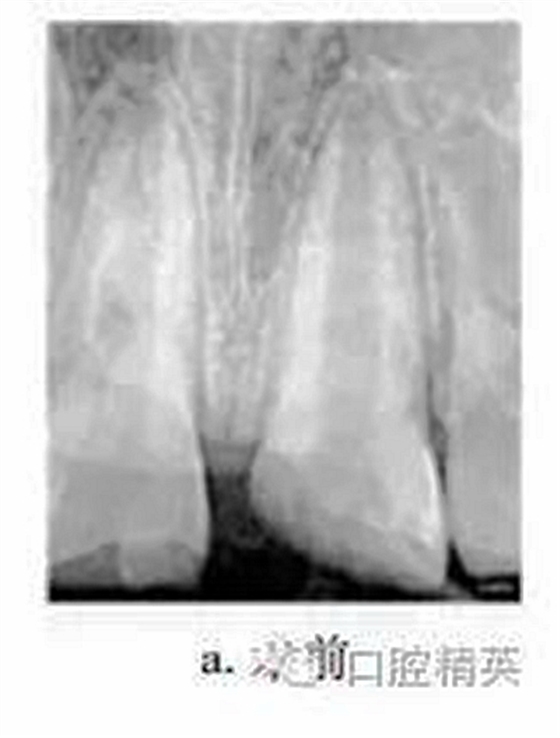

患者男,10歲。2011-06因上頜中切牙外傷就診于我院牙體牙髓病科?;颊咦允?d前患牙外傷,冷熱刺激敏感,但未行治療。檢查:11牙冠近中切角缺失,切緣釉質(zhì)缺損,無松動,探敏感,叩(+),冷熱無明顯不適;21牙冠近中斜折,邊緣銳,髓腔暴露,探診出血,探痛明顯,牙髓電活力測試(-),叩(+),無松動,牙齦未見異常,上唇腫脹。X線片示:21冠部缺損及髓,牙周膜腔增寬,根端管壁呈平行狀,根尖孔未閉合(圖a)。診斷:11釉質(zhì)缺損;21冠折。